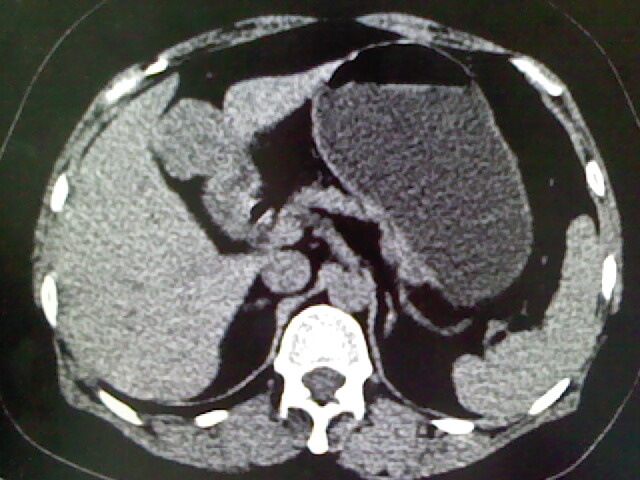

以下是引用卜一在2009-4-2 13:26:00的发言:[br]胆囊颈部结石伴胆囊炎!另:建议增强,待除外肝内占位及胆囊占位!

以下是引用liaoqiang在2009-4-2 16:23:00的发言:[br]胆囊是否切除?胆囊颈区致密影考虑金属夹?结石?肝脏右叶低密度影,考虑增强。